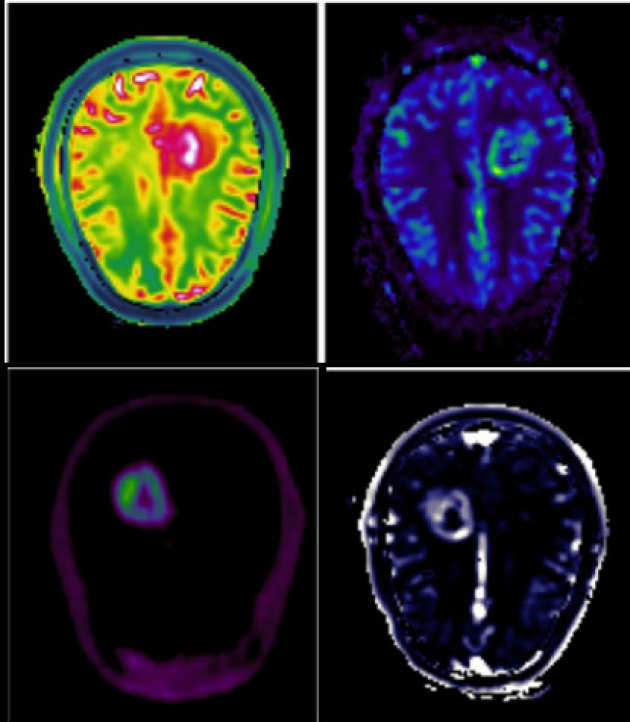

We are investigating imaging biomarkers (diffusion MRI, perfusion MRI, MR Spectroscopy, choline PET) and developing the clinical tools needed to understand brain tumour growth and improve brain tumour diagnosis.

We are applying different pharmacokinetic models to DCE-MRI data to assess blood-brain barrier disruption and leakage in primary brain tumours.

We are investigating the integration of different imaging (DCE-MRI, DWI-MRI, DSC-MRI and PET) techniques for the characterization of tumour tissue.